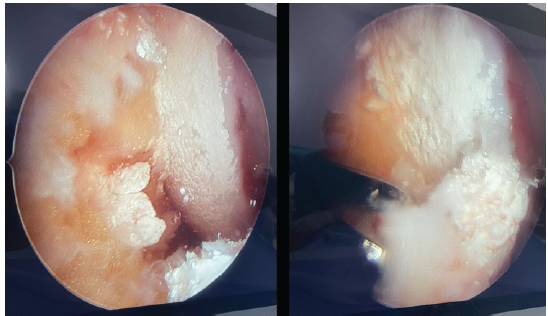

He had no other palpable gouty lesion in the body. He had an elevated serum uric acid of 13.4, with other normal blood parameters. The patient had a pre-operative Lysholm knee score of 35/100. MRI revealed Arthrofibrosis with lateral meniscal tear with mucoid degeneration of anterior cruciate ligament (ACL) with synovitis. The report did not mention any evidence of chondrocalcinosis. Due to the patient’s chronicity of mechanical symptoms and meniscal tear, the patient was taken up for diagnostic arthroscopy. The arthroscopic examination revealed synovitis with widespread chalky deposits over the chondral surfaces, menisci, fat pad, ACL and synovium in the suprapatellar pouch and intra-articularly. (Fig. 2).

Figure 2: (a) Intraoperative arthroscopy images showing chalky white calcium deposits over articular surfaces. (b) Calcium deposits over articular cartilage and anterior cruciate ligament.

The synovial fluid was turbid and there was gross synovial hypertrophy. Samples of the synovium and synovial fluid were collected for histopathological analysis. Arthroscopic debridement of tophi with arthrolysis was done. Partial synovectomy and ACL debulking for mucoid degeneration were done. There was a 3 cm horizontal tear of the anterior horn of the lateral meniscus, which was repaired with outside-in sutures. Post-operatively, pain had decreased, and the patient was kept non-weight bearing for 4 weeks. Quadriceps strengthening exercises were started immediately, and ROM exercises started at 10 days post-operatively. Based on the arthroscopic findings, a provisional diagnosis of chondrocalcinosis was made. The histopathology reported, within the nodular aggregates, which is consistent with tophaceous gout. (Fig. 3). Synovial fluid analysis showed needle shaped crystals suggestive of gout. (Fig. 4). The patient was started on medical management with febuxostat. Post-operative serum uric acid was 7.5. At 6 months follow-up, the patient had a Lysholm score of 80/100. His range of movement had improved was 5° to 120°. The patient was able to carry out his daily activities and had no pain.